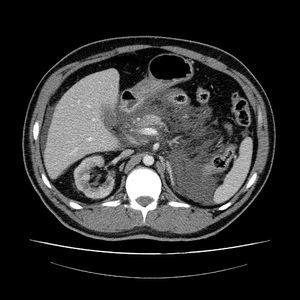

Dos meses después de la retirada del catéter y por preferencia de la técnica, reinicia diálisis peritoneal. A los dos días, acude nuevamente con cuadro clínico compatible con pancreatitis aguda, confirmado con el recuento celular de Leucocitos 153 (26% PMN), Amilasa 418, y la presencia en TAC abdominal de pancreatitis aguda moderada. Al ingreso se inicia tratamiento antibiótico, reposo digestivo y fluidoterapia. Se cesa la diálisis peritoneal, y se transfiere a hemodiálisis. El paciente evolucionó favorablemente. Se realizó peritoneografía TAC no objetivándose paso de contraste a retroperitoneo. Al alta se supendío definitivamente la diálisis peritoneal por su relación temporal con los episodios de pancreatitis. En la actualidad el paciente lleva 14 meses en hemodiálisis , sin haber presentado nuevos episodios de pancreatitis.

Tabla Figura 1.